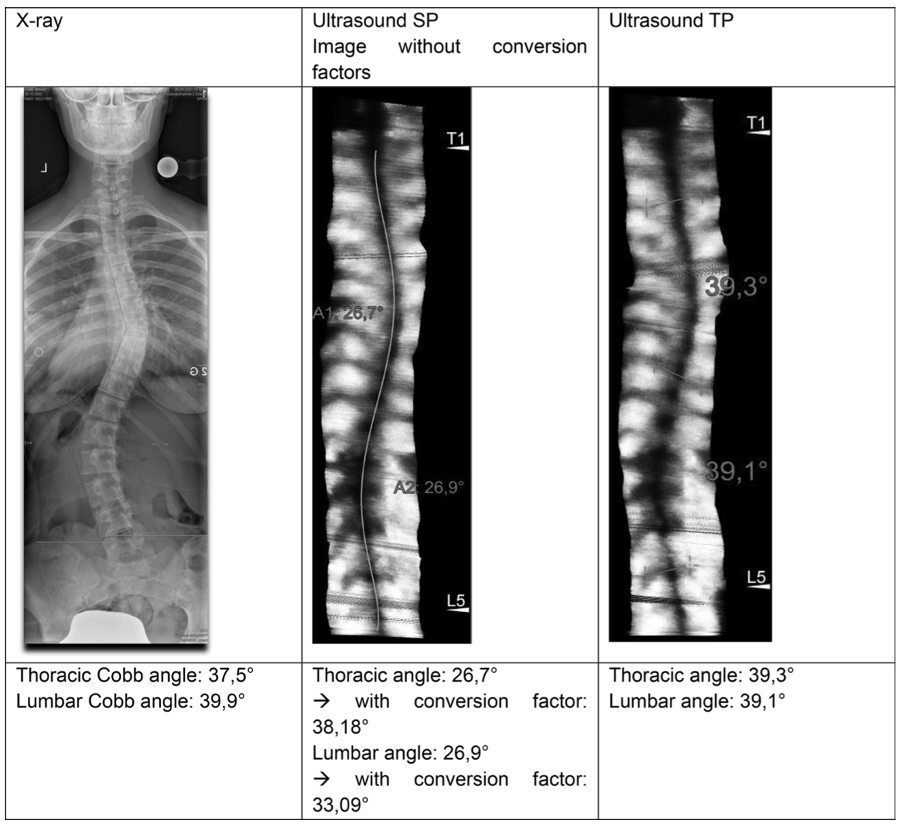

– Comparison of two ultrasound methods from Scolioscan® for measuring spinal curvature: spinous processes (SP) versus transverse processes (TP) (2025)

This study compared the validity and reliability of two Scolioscan® automatic ultrasound measurement methods based on the spinous processes (SP) and the transverse processes (TP) against the gold‑standard Cobb angle from standing anterior–posterior X‑rays in 71 adolescent idiopathic scoliosis patients. All patients underwent both X‑ray and ultrasound assessment on the same day. SP-based angles were multiplied by region‑specific conversion factors (1.43 for thoracic, 1.23 for lumbar), whereas TP‑based measurements required no conversion.

Example of a patient with the according X-ray image, ultrasound images based on SP and TP

Key Findings

- SP method: Thoracic ICCs ranged from 0.871–0.900. Lumbar ICCs ranged from 0.702–0.799.

- TP method: Thoracic ICC = 0.893 (95% CI 0.834–0.932). Lumbar ICC = 0.888 (95% CI 0.823–0.929).

- Both methods achieved ≥ good reliability, with TP showing marginally higher and more consistent ICCs, especially in the lumbar region.